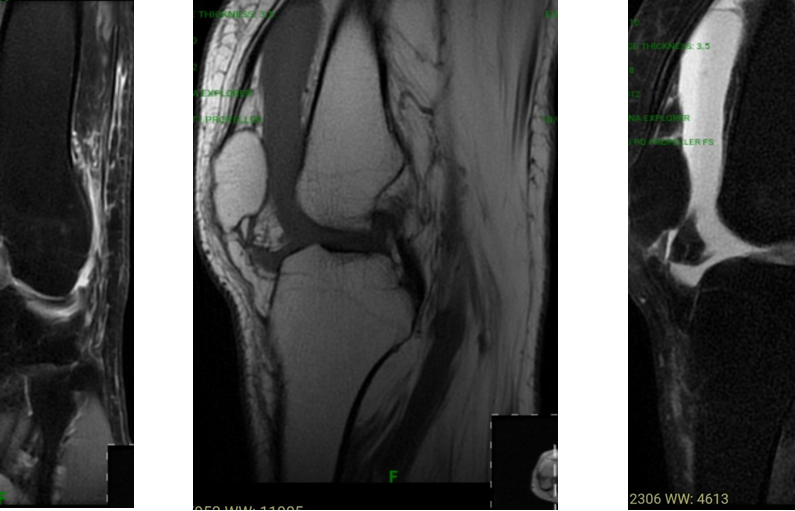

Magnetic resonance imaging (MRI) scan of the knee (Figs. 3 and 4) revealed a complete tear of the anterior cruciate ligament (ACL), the medial collateral ligament (MCL), and a tear of the anterior horn and part of the body of the lateral meniscus.

Figure 3: Magnetic resonance imaging scan left knee (showing Complete tear of ACL and MCL).

MRI left knee (Figs. 3 and 5) was suggestive of a near-complete ACL tear, a Grade II tear of the anterior horn of the lateral meniscus, and a tear of the medial collateral ligament.